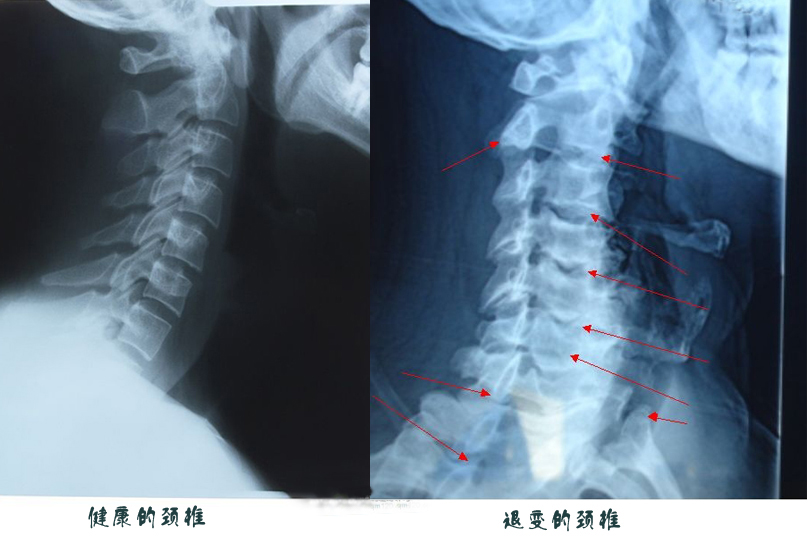

台中中港醫院復健科醫師楊鎮嘉直言,自己也被這名男子的頸椎X光嚇到,其第4、5、6節的椎體變形,間隔變窄,還有明顯的骨刺,已壓迫到神經,看起來就像70多歲老人已經退化的頸椎。這與他經常長時間玩手機的習慣不無關係。

低頭族頸椎易提早退化 禍起頸椎第4、5、6節

楊鎮嘉說,一般脊椎慢性退化病變都出現在頸椎第5、6、7節,低頭族則在第4、5、6節。以前患者多是生產線的作業員,現在則大多是手機低頭族,各個年齡段都會發生。尤其是經常躺臥在床上玩手機,頸椎彎曲角度更大,症狀加速惡化,如不改善,甚至要開刀治療。